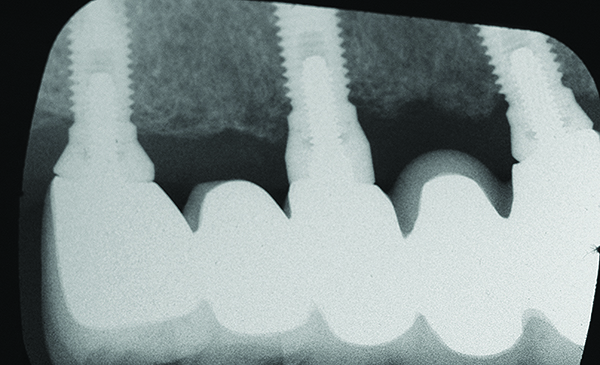

Fig 7 through Fig 14. Periapical radiographs of a 62-year-old woman who received a fixed porcelain-fused-to-metal reconstruction supported by abutments by internally connected dental implants. Fig 7 through Fig 10 are at initial prosthesis placement: mandibular site Nos. 30 and 29 (Fig 7); mandibular site Nos. 26, 25, and 23 (Fig 8); mandibular site Nos. 23 and 21 (Fig 9); mandibular site Nos. 21 through 19 (Fig 10). Fig 11 through Fig 14 are 11 years later (2013) and show excellent preservation of the vertical bone levels around the implants: mandibular site Nos. 30 and 29 (Fig 11); mandibular site Nos. 26 and 25 (Fig 12); mandibular site Nos. 25 and 23 (Fig 13); mandibular site Nos. 20 and 19 (Fig 14). It is interesting to note that in the mandibular right posterior quadrant there is a matched pair, ie, an external hex dental implant (No. 30) adjacent to an internally connected dental implant (No. 29). The bone levels around each of these designs are well-preserved at the 11-year follow-up.